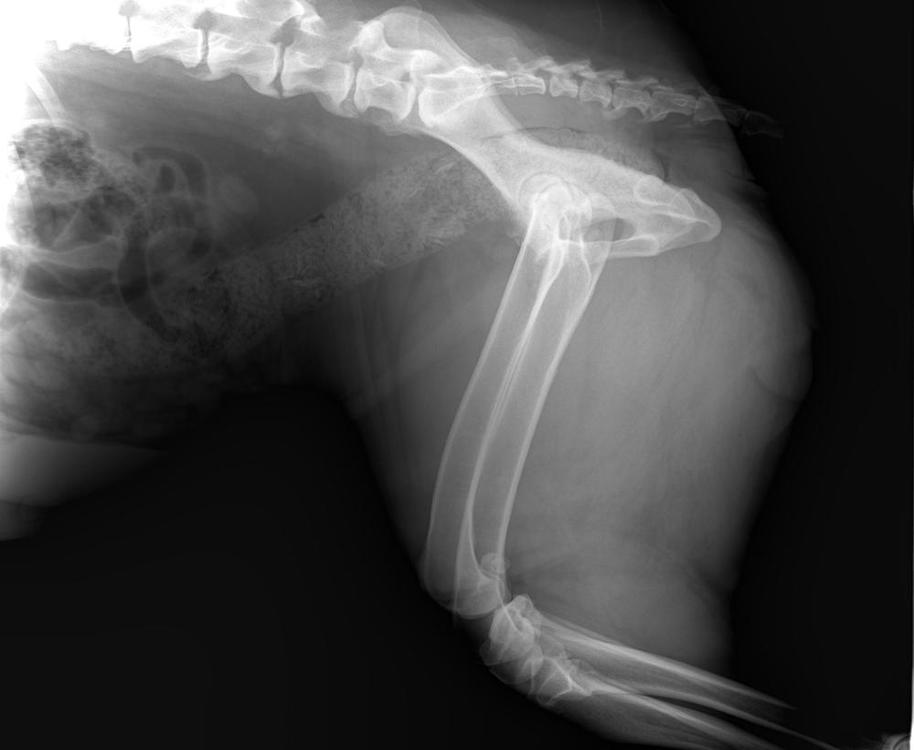

Бэкки Опубликовано 19 апреля, 2019 Опубликовано 19 апреля, 2019 Добрый день! Съездили вчера с Дусенькой к доктору, при осмотре доктор сказал, что до конца не сгибаются локтевые суставы, тазобедренные вопросов не вызвали, сделали рентген локтевых суставов и поясничного отдела. Результаты ниже. Снимки записаны на диск, но у меня нет дисковода)) Муж сможет днем на работе открыть и переслать мне, если нужны. Рекомендовано худеть и худеть на много, до 30 кг, а сейчас Дусенька 35,5 кг. , противовоспалительное пока не назначил, считает, что снижение веса значительно облегчит состояние, а пить лекарства еще успеем. Так что, будем много плавать, это нам можно, и мало кушать) 1 5